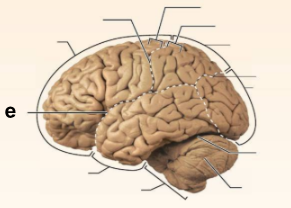

Identify the structure labeled “a” in the image.

Brain Stem

Identify the structure labeled “b” in the image.

Central culcus

Identify the structure labeled “c” in the image.

Cerebellum

Identify the structure labeled “d” in the image.

Frontal lobe

Identify the structure labeled “e” in the image.

Lateral sulcus

Identify the structure labeled “f” in the image.

Occipital lobe

Identify the structure labeled “g” in the image.

Parietal lobe

Identify the structure labeled “h” in the image.

Parieto-occipital sulcus

Identify the structure labeled “i” in the image.

Postcentral gyrus

Identify the structure labeled “j” in the image.

Precentral gyrus

Identify the structure labeled “k” in the image.

Temporal lobe

Identify the structure labeled “l” in the image.

Transverse cerebral fissure